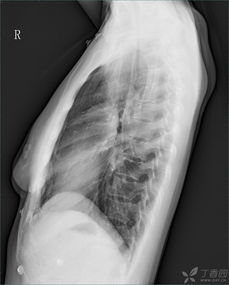

膈肌位于胸腔底部,形状像一把撑开的雨伞,它通过收缩和放松来调节呼吸。当你吸气时,膈肌收缩,向下移动,胸腔空间增大,肺部扩张,空气自然就进来了。呼气时,膈肌放松,向上移动,胸腔空间减小,肺部收缩,空气就排出了体外。

随着年龄的增长,我们的膈肌也会逐渐退化。老年人胸廓和膈肌的退行性变,以及腹腔内脂肪的增加,都会限制膈肌的运动,影响呼吸功能。这就是为什么老年人容易出现呼吸困难、咳嗽等症状的原因。